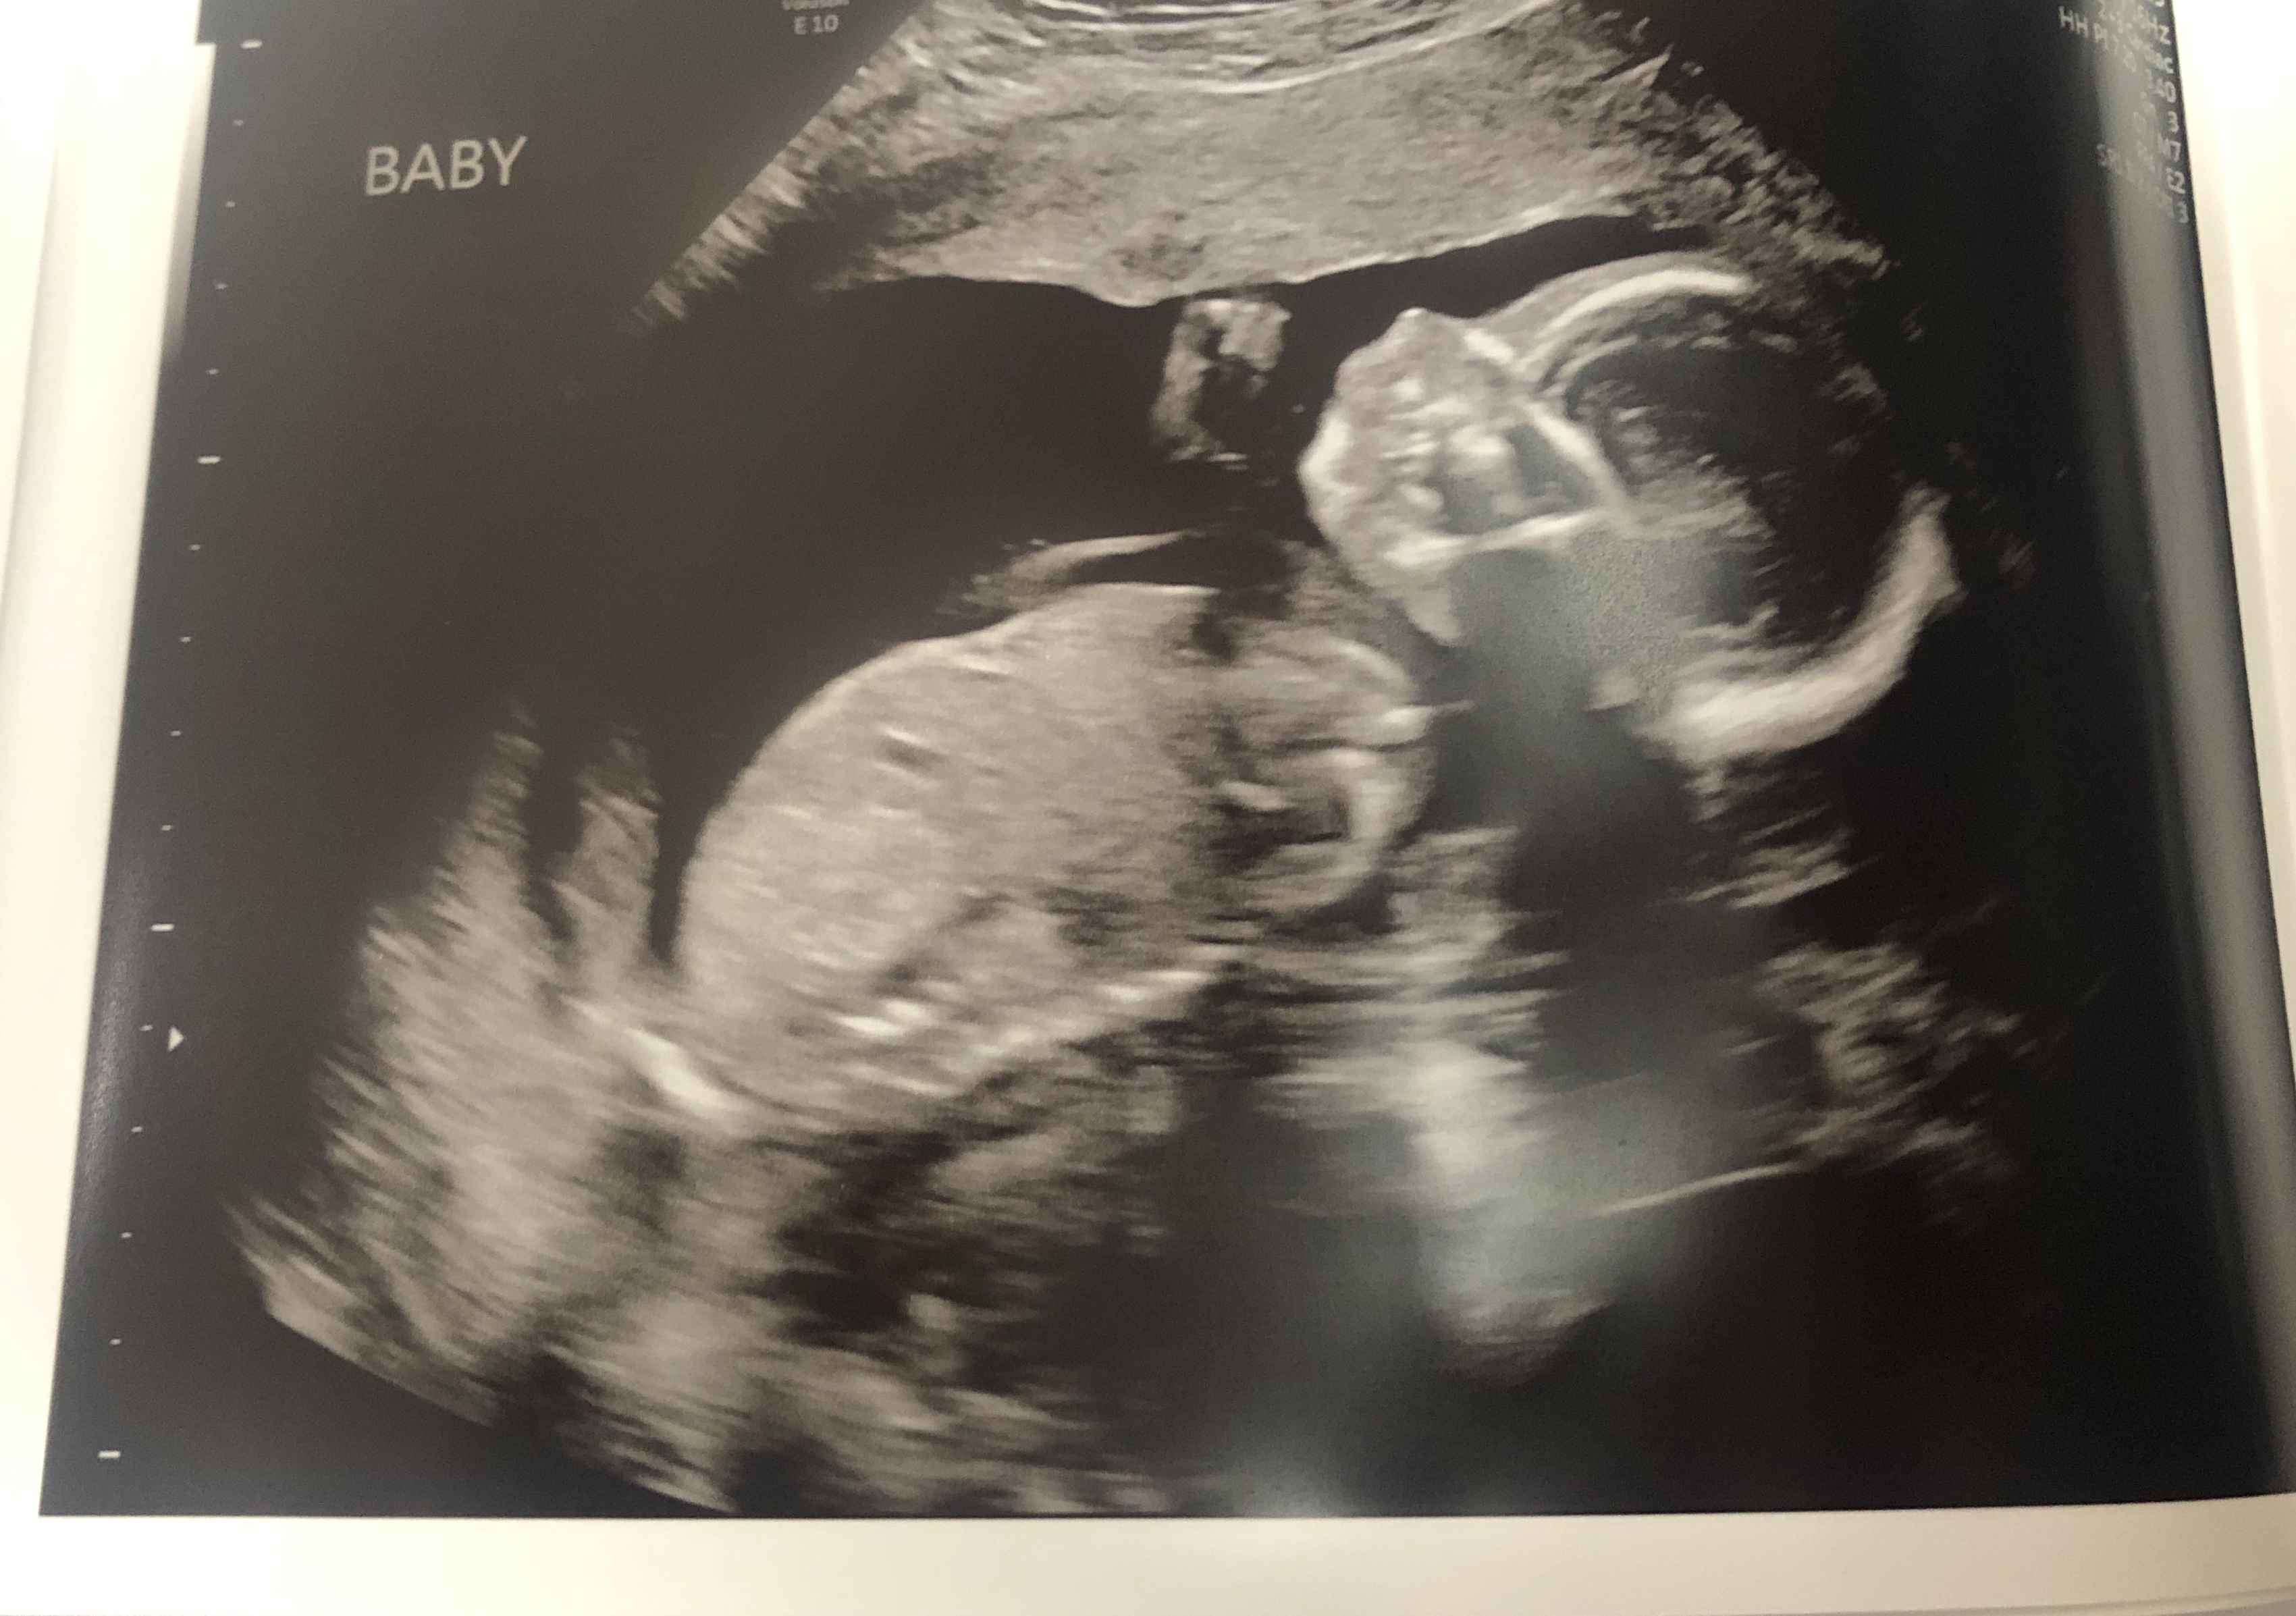

My baby and her little feet (top picture)!🦶🥰 19w4d